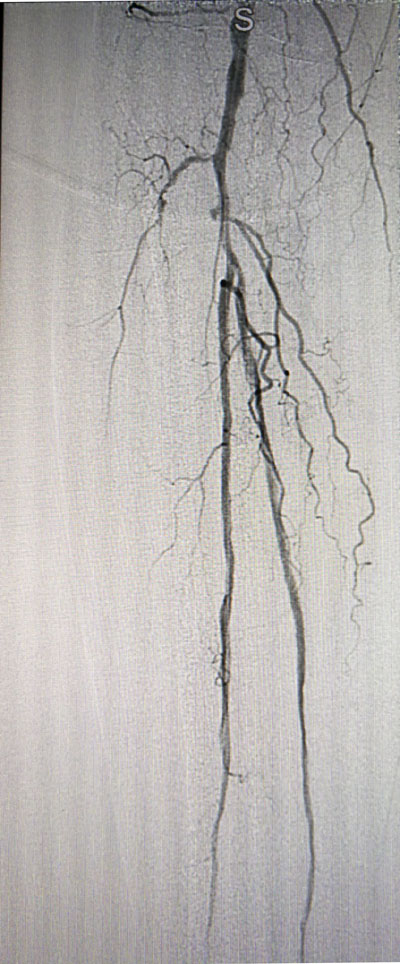

放射科導管室內做好了術前準備,患者由無創呼吸機及各種循環支持下開始介入手術,術中重癥監護科嚴密觀察患者的生命體征,內分泌科醫生負責手術,患者下肢血流極差,膝下僅存一條多處嚴重狹窄的腓動脈供血,主要供血的脛前動脈及脛后動脈均長段閉塞,順行穿刺成功后導絲下行困難,故采用踝下脛后動脈逆穿對接技術成功通過病變。經過近5個小時的奮斗,手術順利完成,患者腓動脈及脛后動脈血流通暢,血流直達足底動脈環,患者感到足部逐漸溫暖,術后清創時患者創面血流豐富。

治療后